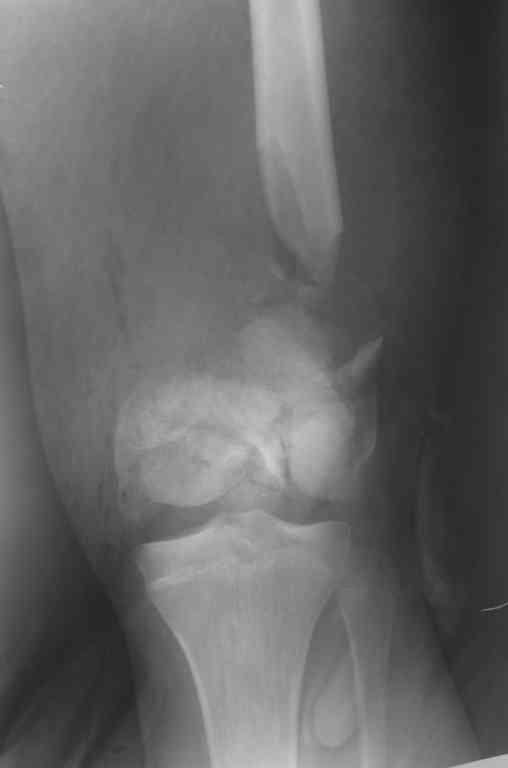

Внутрисуставной перелом бедренной кости

Уважаемые коллеги! Хотелось бы услышать ваше мнение по тактике лечения перелома бедра.

Пациент 17 лет. Травма 07.10.2006 - попал под грузовик. Рана на бедре зажила первичным натяжением. Мы рассматриваем следующие варианты: открытая репозиция + 1)остеосинтез аппаратом внешней фиксации; или 2)фиксация пластиной LCP. Ваши предложения? Как бы вы поступили с имеющимся дефектом бедренной кости?Екатерина Анатольевна Озерова

Глубокоуважаемая Екатерина Анатольевна !IMHO АВФ следовало бы поставить еще на этапе ПХО.При монтаже АВФ стоит предусмотреть возможность выращивания регенерата,а возможно,и модуль на коленный сустав для ранних движений.после выращивания регенерата можно,наверное,будет закрыто заштифтовать,но это вопрос будущего.Не совсем ясно,что там с надколенником.Хотелось бы уточнить,локальный статус на момент поступления и объем первичного вмешательства(в частности был ли вскрыт сустав)Ставить LCP на таком переломе,в условиях рубцов и при наличии дефекта-удовольствие еще то!

Картинка конечно страшненькая, но можно рискнуть и не открываться.

Внешняяя фиксация тем и хороша, что позволяет получать нормальные ФУНКЦИОНАЛЬНЫЕ результаты при жуткой анатомии. Попробуйте собрать закрыто. Адаптация возможна постепенная. Важно суставные поверхности сохранить конгруетными. постепенно загоните"шип" проксимального отломка в ценр мышелков и на фиксацию.